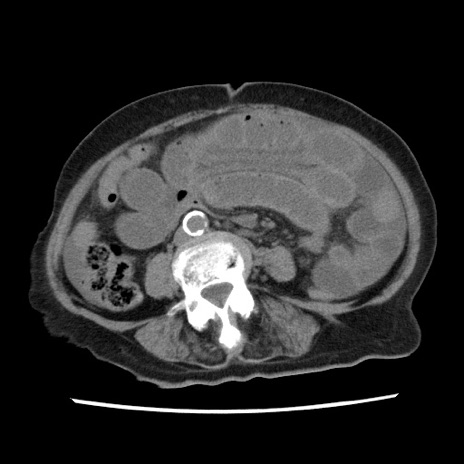

症例1(横断像)

【症例】80歳代女性

【主訴】腹痛

【現病歴】8時間前から腹痛あり来院。

【既往歴】糖尿病、脂質異常症、子宮体癌にて子宮全摘術

【身体所見】意識清明・会話良好だが腹痛で苦悶様、全腹部にわたって反跳痛と圧痛あり

【データ】WBC 13600、CRP 0.14、LDH 224、CK 90